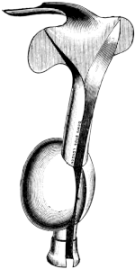

| 209. | Eustachian Catheter | 365 |